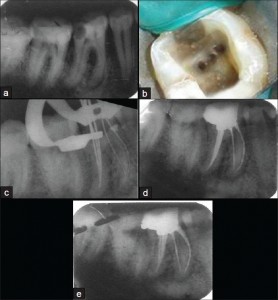

- CASE DISCUSSION & ESTABLISHING DIAGNOSIS WITH RADIOGRAPHS

- BMP WITH MANUAL & ROTARY TECHNOLOGY

- WORKING LENGTH DETERMINATION WITH APEX LOCATORS

- RETREATMENT FOR AN EXISTING RC TREATED TOOTH [demo only]

- re-treatement in a RC Treated failed tooth!